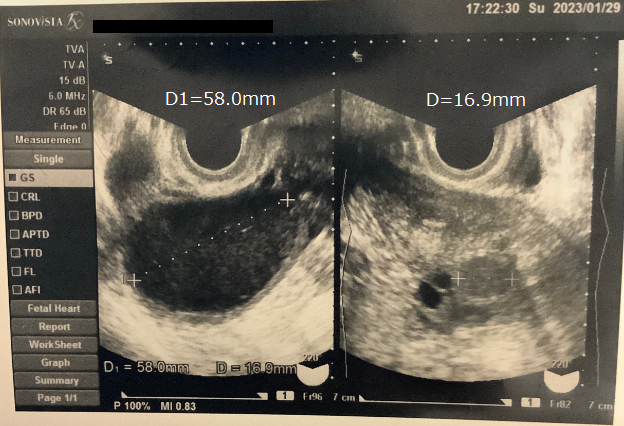

【改善の実例】

・漿液性・粘液性嚢腫 2〜3cm減少する方、現状維持の方など様々です。10cmを超える大きなサイズの場合は、リスクを正直にお伝えした上で、婦人科と連携しつつ最善の道を一緒に考えます。